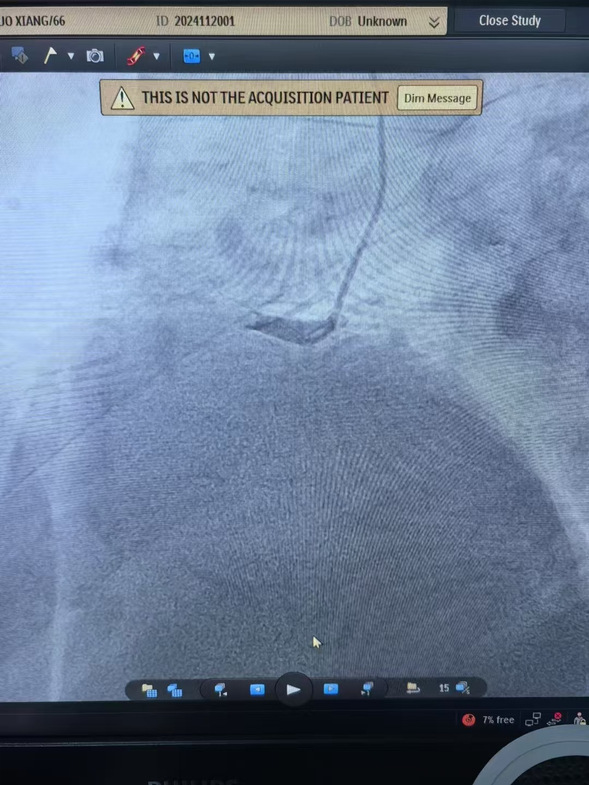

早7点,患者经120迅速到达我院大门,此时患者面色苍白、出汗明显、疼痛难止。我院医务人员立即通过绿色通道绕行急诊和病房,以最快速度将患者转移到介入手术室。在规范执行胸痛中心双绕流程基础上,心血管内四科主任沈彦祥带领医生孙智睿经临时起搏、血栓抽吸,患者胸痛症状得以缓解,状态良好。

术前、术中、术后影像